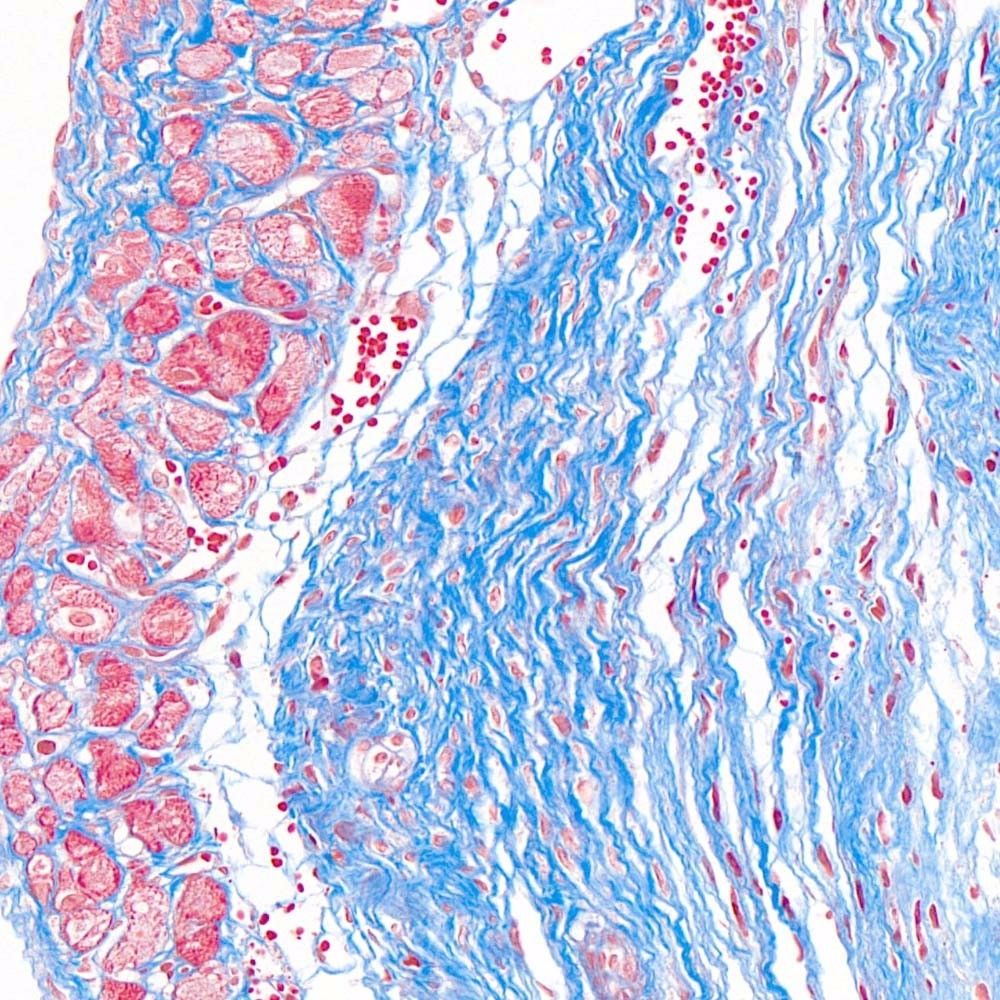

首先,讓我們深入探討MASSON染色的原理。MASSON染色的原理與陰離子染料分子的大小和組織的滲透性密切相關。染料的分子量決定了其穿透組織的能力:小分子量的染料更容易穿透結構致密、滲透性較低的組織,而大分子量的染料則更傾向于進入結構疏松、滲透性較高的組織。在MASSON染色中,由于肌纖維間隙較小,而膠原纖維間隙較大,因此小分子量的麗春紅染料更容易滲透進入肌纖維并使其呈現紅色,而大分子量的苯胺藍染料則主要進入膠原纖維并使其呈現藍色或綠色。

MASSON染色的陽性意義在于,它能夠幫助研究人員區分膠原纖維和肌纖維,從而觀察病變組織中纖維結締組織的增生和分布。當MASSON染色結果呈現陽性時,通常意味著局部組織中存在膠原纖維的增生。這種增生可能是由于局部皮膚出現炎癥或組織增生等病理 過程所導致的。因此,MASSON染色的陽性結果可以作為判斷組織纖維化程度的一個重要指標。